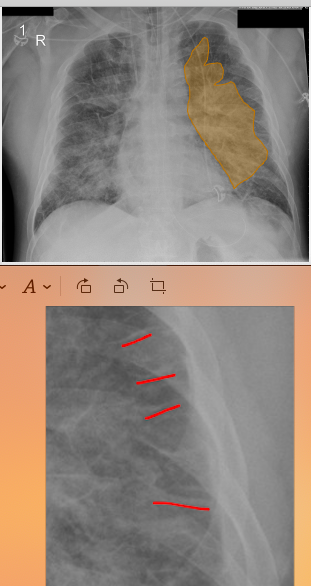

What is the major pathological finding in this image ? Pleural effusion Pulmonary oedema Cardiomegaly Heart Valve Normal CXR

What is the major pathological finding in this image ? **Pleural effusion** Pulmonary oedema Cardiomegaly Heart Valve Normal CXR *There is a moderate right-sided pleural effusion. There is a meniscus and opacification clearly visible into the midzone of the right lung.*